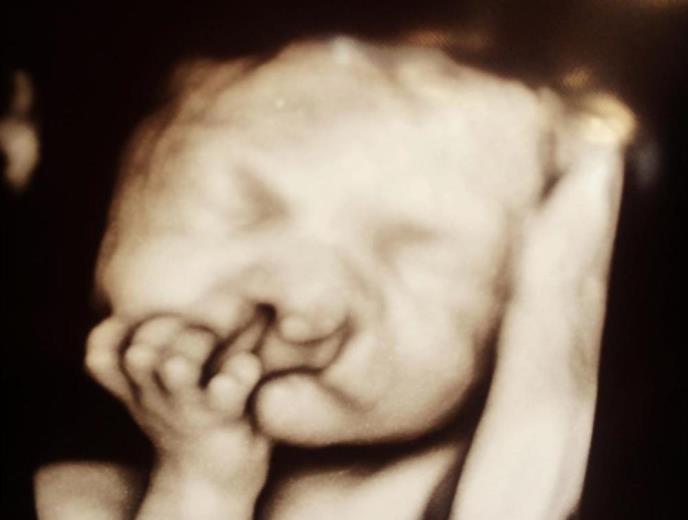

Ultrazvuk je pokazao da će dečak biti rođen s rascepom usne i nepca zbog čega će imati i brojne druge zdravstvene probleme, pa su joj savetovali da ipak izvrši abortus.